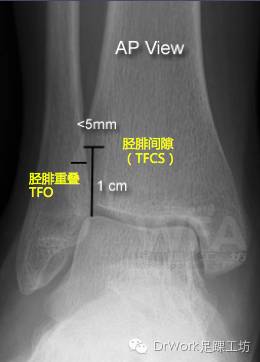

X片复位标准

正位片

• TFCS<5mm

• TFO>5mm

踝穴位片

• TFO>1mm

下胫腓间隙增加(TFCS)是其中最有效指标

• 投射角度外旋5o至内旋25oTFCS均无明显变化----适合诊断